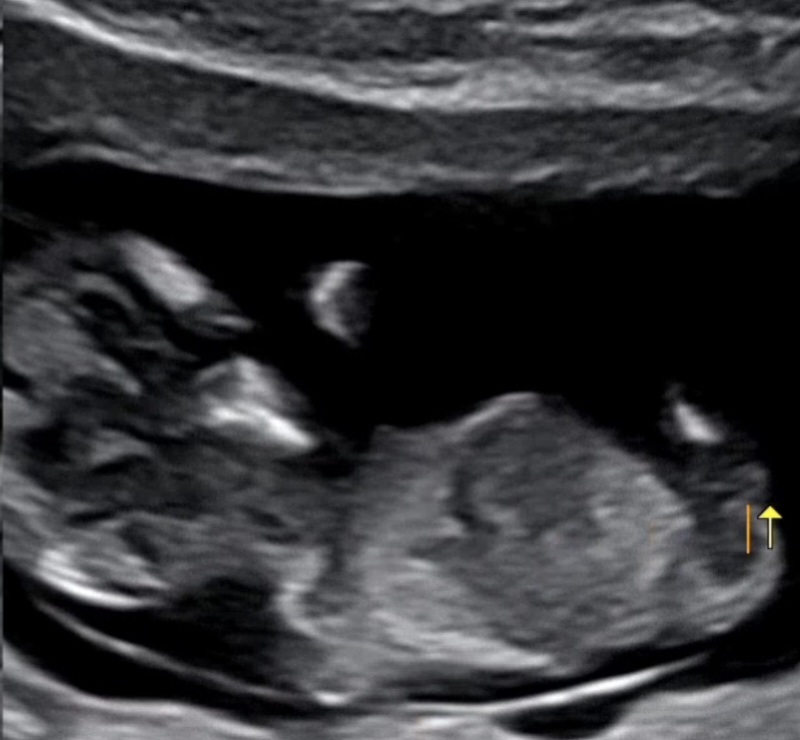

딸?아들? 11주 4일 각도법 봐주세요 ㅠㅠ

딸일까요 아들일까요?